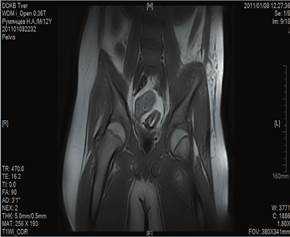

При поражении зоны эпифиза выявлялись патологические изменения суставных структур, нарушение их формы, уменьшение толщины, «изъеденность» хряща, признаки остеосклероза субхондральной зоны. На поздних сроках заболевания секвестры отчетливее определяются на КТ, МРТ несколько уступает в визуализации кортикального слоя кости. У пациентов с метаэпифизарным остеомиелитом в возрасте от 0 до 3 лет выполнено 21 исследование (21,6%). МРТ проводилось в 3 случаях при септической форме заболевания. В 10 (47%) случаях МРТ-исследование использовалось в качестве уточняющей методики в интрамедуллярную фазу на 1-3-и сутки от момента поступления при недостаточной информативности УЗ и рентгенологического методов. В 8 (38%) случаях МРТ применялось при поступлении пациентов на 4-7-е сутки заболевания (рис. 3, 4).

Рис. 4. Томограмма (МРТ) тазобедренных суставов. ОГО левой подвздошной кости, 7-е сутки